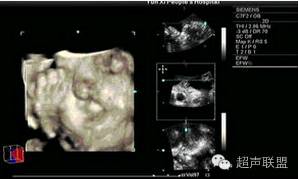

超声检查:最佳检查孕周为28周左右,羊水衬托好,从纵、横及冠状切面连续动态扫查,观察可见到唇弓回声中断,呈分又征,根据发生侧别和程度可有不同表现。合并腭裂时于门齿后方融合不全,造成腭开放,鼻腔相通,此时上唇结构消失,鼻小、向健侧移位,患侧鼻翼内陷。两鼻孔距离增大,或仅见一鼻孔(严重腭裂时)。超声对唇裂的检出率国内报道达852%,产前诊断率根据胎儿大小、胎位和胎儿面部有无羊水衬托有关,诊断的经验性也很强。近年来开展的四维超声能够对胎儿面部进行立体成像,直接得出类似拍照片的立体效果,使面部病变一目了然,进一步提高了唇裂的检出率。

胎儿唇腭裂三维超声表现

所见唇裂典型者呈"^" "" 字形,轻者裂口断端无明显增厚,鼻外表形态正常,双鼻孔同等大小且对称;重者裂口断端厚薄不等,鼻外表形态失常,双鼻孔不对称且大小不一。

单侧完全唇裂伴牙槽突裂或完全腭裂,三维超声可见鼻唇外表形态严重失常,结构紊乱,鼻梁塌陷变形,上唇部分缺失,鼻唇间存在不规则孔洞,有时可见与鼻腔连为一体;

双侧发生时,鼻唇之间结构紊乱,上唇不清,鼻下方有不规则团块且明显前突。对于完全唇裂伴牙槽突裂或完全腭裂,三维超声表面成像仍存在一定局限性,因难以区分构成图像的结构是软组织还是骨质,此外,鼻部塌陷时易与缺损的颌部形成重叠像,加之受限制条件更多。所以,三维超声不能代替二维超声检查,在一定程度上起到补充完善作用。